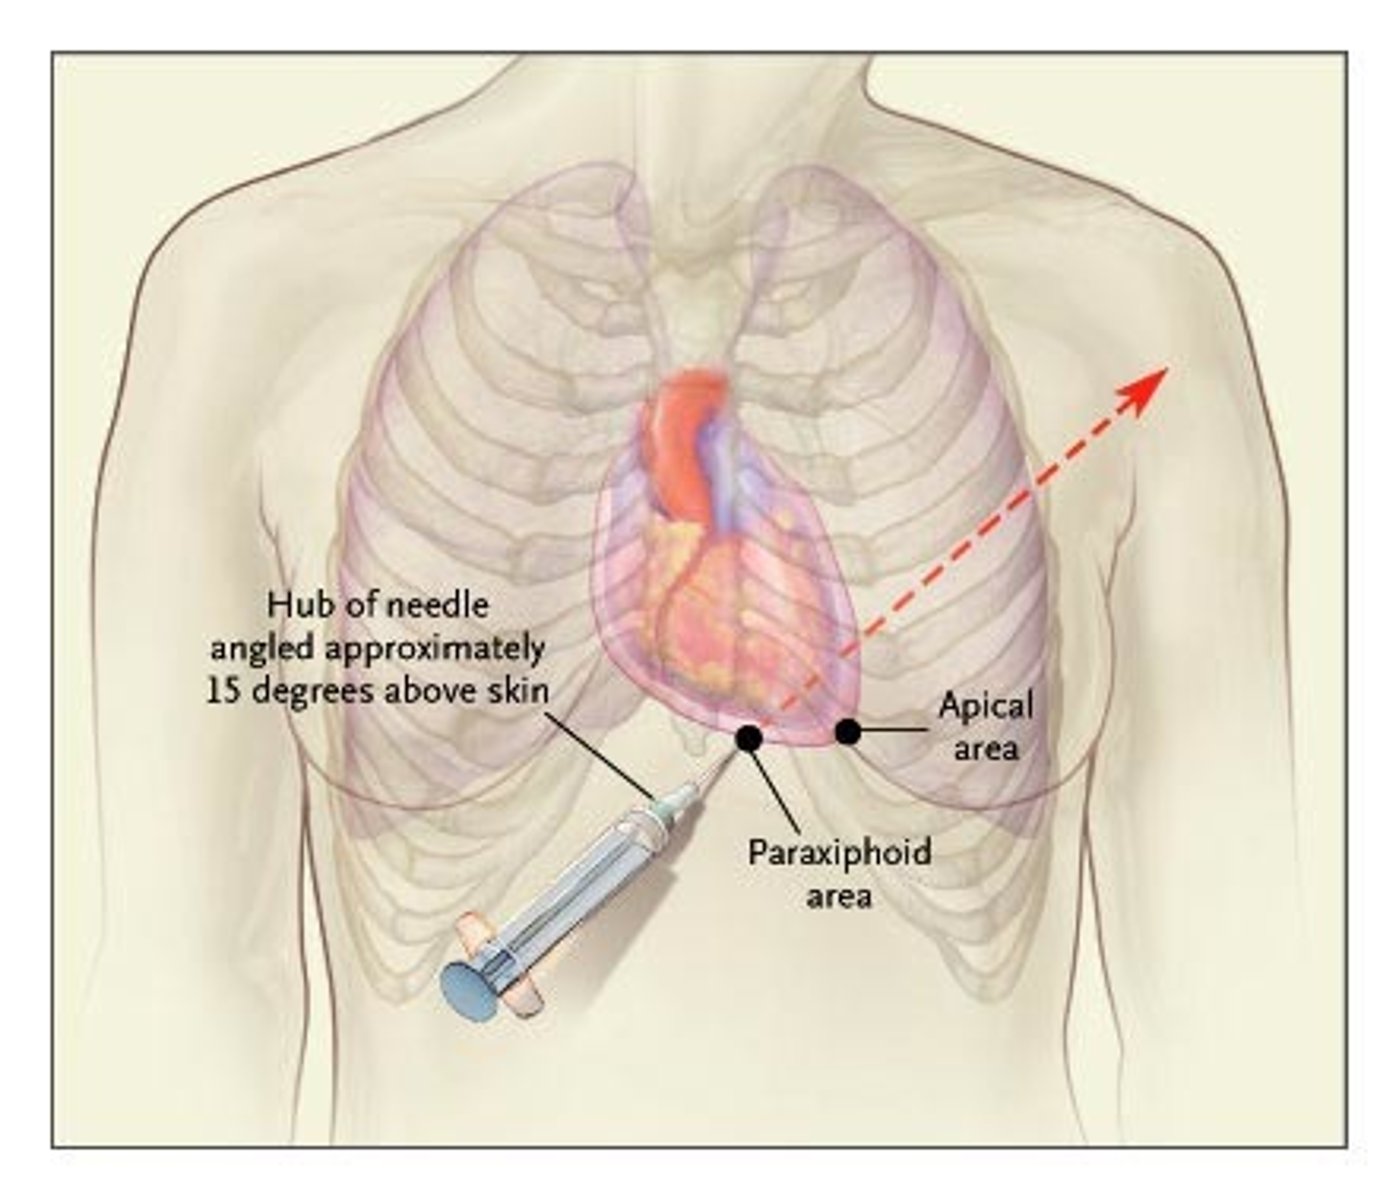

Jaki jest skutek nagromadzenia dużej ilości płynu w jamie osierdzia?

uciśnięcie serca - tamponada serca